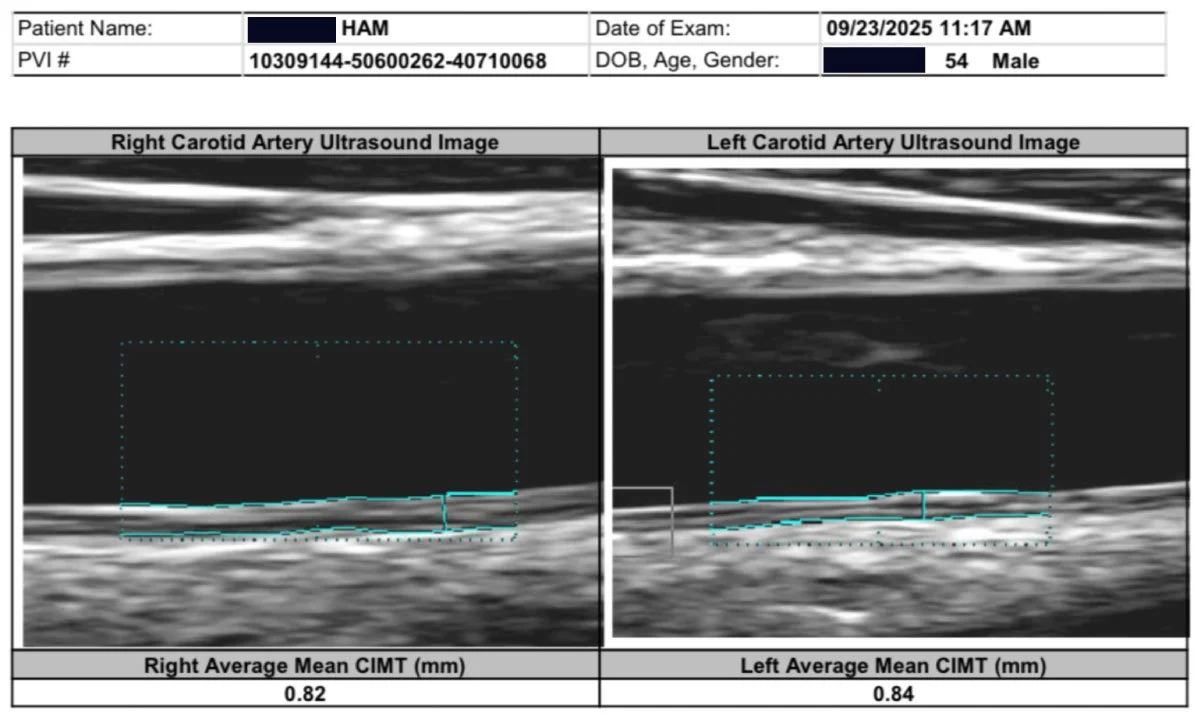

As you may know, I had bilateral plaque in the carotid arteries, now all gone. It seems almost miraculous, so I am studying the studies to understand the mechanism of how and what happened for such a remarkable result. I have reviewed the major carotid artery studies on exercise.

20 micrometres across 26 trials is a real effect, but a modest one. It is the average of every kind of exercise at every dose at every duration. My own carotid moved 700 micrometers in 90 days. 35 times the pooled effect. That gap is the question this whole series exists to answer.

This is 24 minutes of High Intensity and 18 minutes of Interval, so the total time is 42 minutes. At 3 times per week, that is 2 hours 6 minutes. I do 4x this amount. And I had 53% CIMT reduction in 12 weeks.

After thinking how I reversed my carotid plaque from May 9, 2025 (Started WFPB Esselstyn diet) to August 19, 2025, when my carotid ultrasound showed that all my plaque was gone and CIMT reduced 53%, I have been trying to understand the mechanism and biochemical pathways this occurred. I have been so focused on diet, that I wondered how much my 3000 km of cycling played a role. I did three Gran Fondo (120+ km) rides last year. Then after my September fondo, I basically stopped riding. My coronary plaque did not really reverse after that, although blood flow improved remarkably. So that has made me curious.

The carotid ultrasound at three months showed something I had hoped for but had not been certain enough to expect: both carotid arteries were completely clear. Not reduced. Clear. The plaques had resolved bilaterally in just three months. And the CIMT, the intima-media thickness that had read like an 85-year-old when I started, crossed into high-normal for age 55. By month ten, it was mid-normal. A 53% bilateral reduction in carotid arterial wall thickness, confirmed on imaging another three times afterwards, always improving.